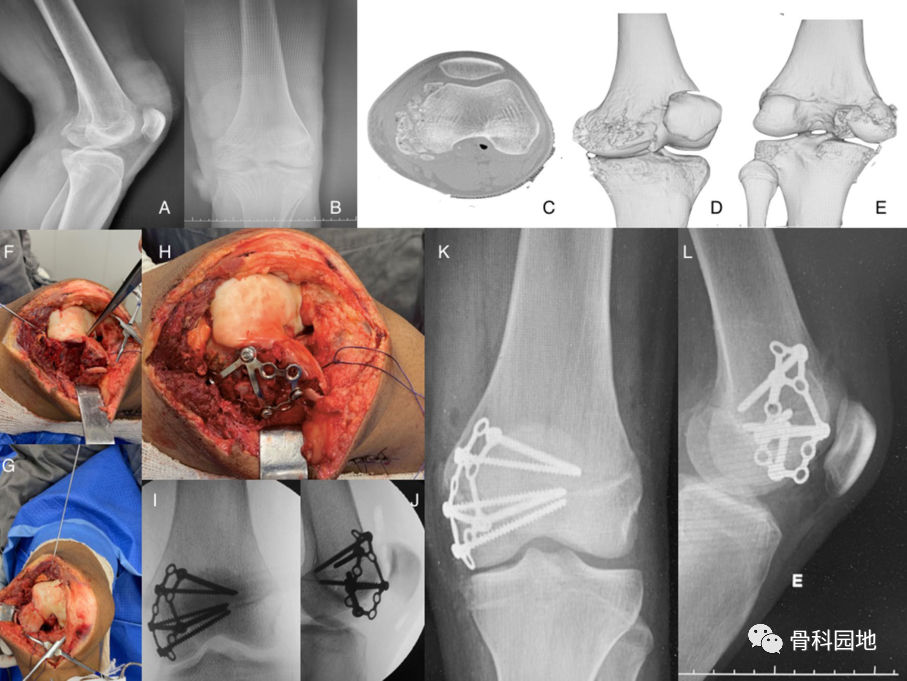

四、股骨内侧髁骨折

股骨内侧髁粉碎性骨折,应用跟骨板复位固定。主要指征是严重粉碎骨折。但如果存在剪切力,单个跟骨板可能不足以 支撑该力。

五、髌骨骨折

四颗 3.5mm 皮质螺钉用作拉力螺钉,两颗从上到下,两颗从下到上多个方向固定